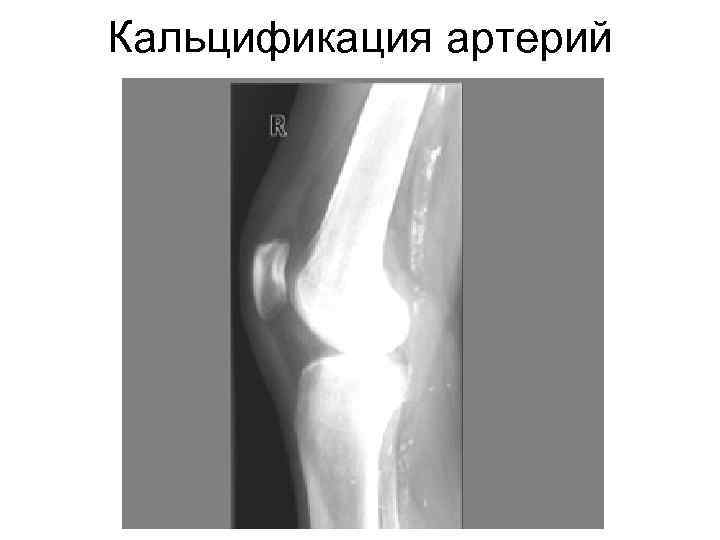

Кальцификация артерий

Кальцификация мягких тканей при почечной остеодистрофии